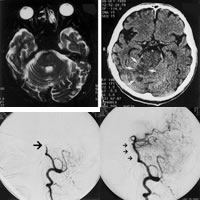

图1 脑干磁共振成像显示基底动脉无血流

图2 CT提示右侧小脑缺血性改变

图3 动脉内数字减影血管造影显示基底动脉闭塞(如箭头所示)

图4 溶栓治疗后基底动脉恢复再灌注(如箭头所示), http://www.100md.com